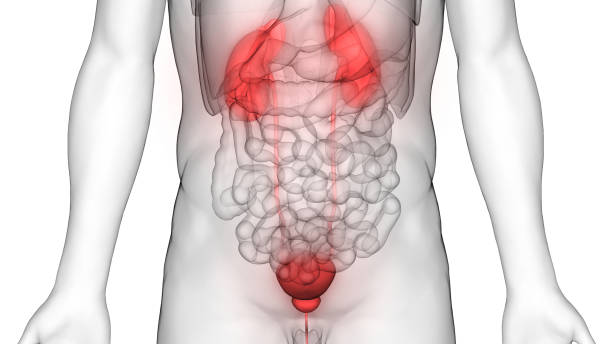

대부분 하부 요로계, 즉 방광이나 요도에서 시작된 세균이

상행성으로 올라가 신장 부위까지 확산되며 생깁니다.

- 방광염, 요도염에서 감염이 확산

- 요로결석으로 소변 흐름이 막히는 경우

- 임신 중 자궁이 요관을 압박해 소변 정체